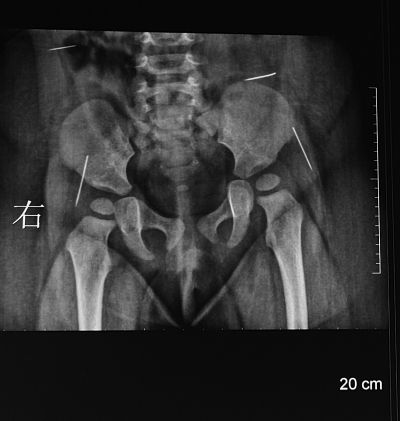

“一根、两根、三根、四根,这是右侧腰部一根,这是左侧腰部,这是臀部的,像缝衣针,还有像大头针,三厘米,臀部这两根很长,腰上两根1.5厘米差不多……”淮安市妇幼保健院手术医生夏顺林拿着女婴的X片向记者介绍。